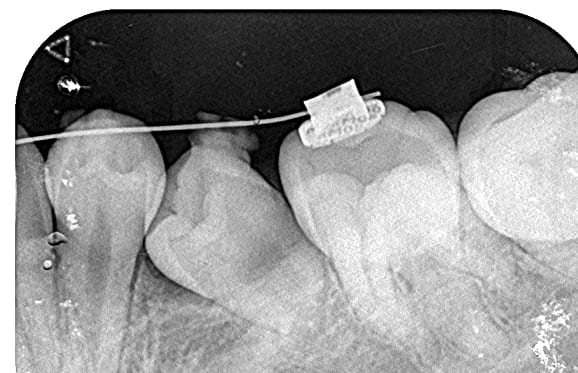

● C4を超え歯根までの虫歯を抜歯、スペースを利用して歯並び全体を整えた症例

藤沢デンタルオフィスの虫歯や破折で抜歯後の部分矯正